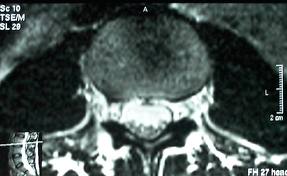

Imagem de Ressonância com Estenose grave do canal lombar.

Note a diferença de uma Ressonância de um canal vertebral normal.